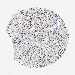

PANCREATIC CANCER - Protein expressioni

A mouse-over function shows sample information and annotation data. Click on an image to view it in a full screen mode. Samples can be filtered based on level of antibody staining by selecting one or several of the following categories: high, medium, low and not detected. The assay and annotation is described here.

Note that samples used for immunohistochemistry by the Human Protein Atlas do not correspond to samples in the TCGA dataset.

Antibody stainingi

Antibody staining in the annotated cell types in the current human tissue is reported as not detected, low, medium, or high, based on conventional immunohistochemistry profiling in selected tissues. This score is based on the combination of the staining intensity and fraction of stained cells.

Each image is clickable and will lead to virtual microscopy that enables deeper exploration of all samples and also displays staining intensity scores, fraction scores and subcellular localization as well as patient and tissue information for each sample.

Antibody CAB012342

Staining

High

Medium

Low

Not detected

Intensity

Strong

Moderate

Weak

Negative

Quantity

>75%

75%-25%

<25%

None

Location

Nuclear

Cytoplasmic/membranous

Cytoplasmic/membranous,nuclear

Adenocarcinoma, NOS

Adenocarcinoma, metastatic, NOS